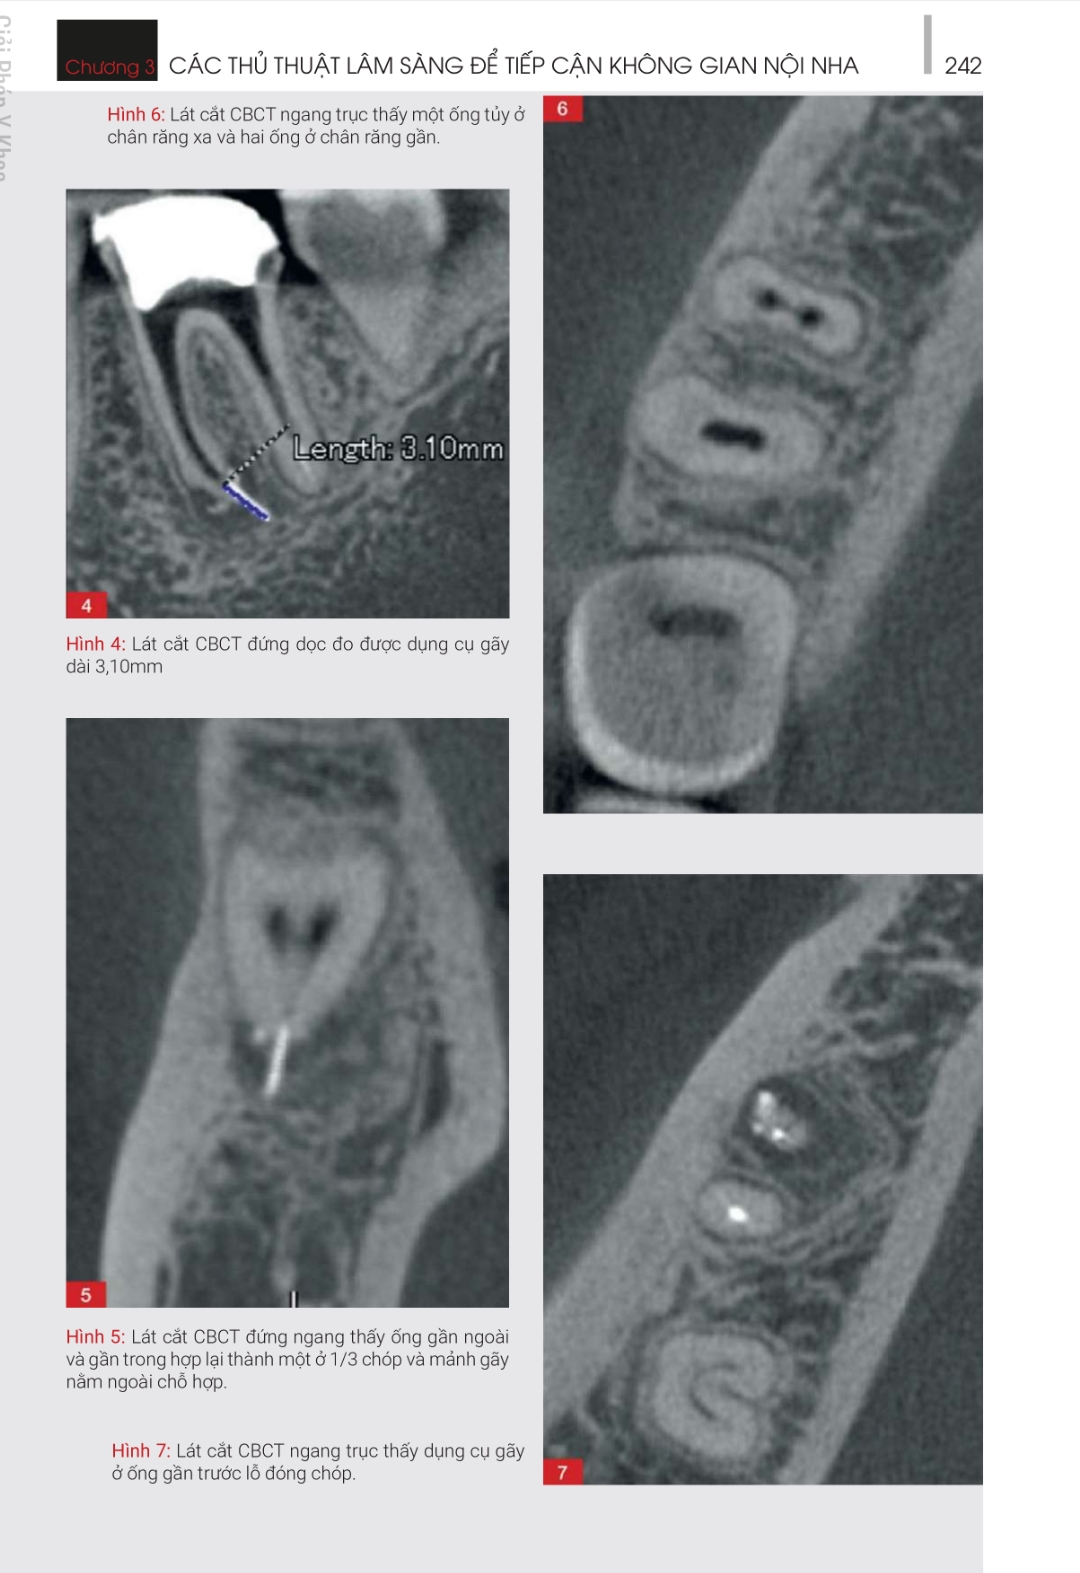

ĐIỀU TRỊ LẠI – NHỮNG GIẢI PHÁP SANG THƯƠNG QUANH CHÓP NGUỒN GỐC TỪ NỘI NHA